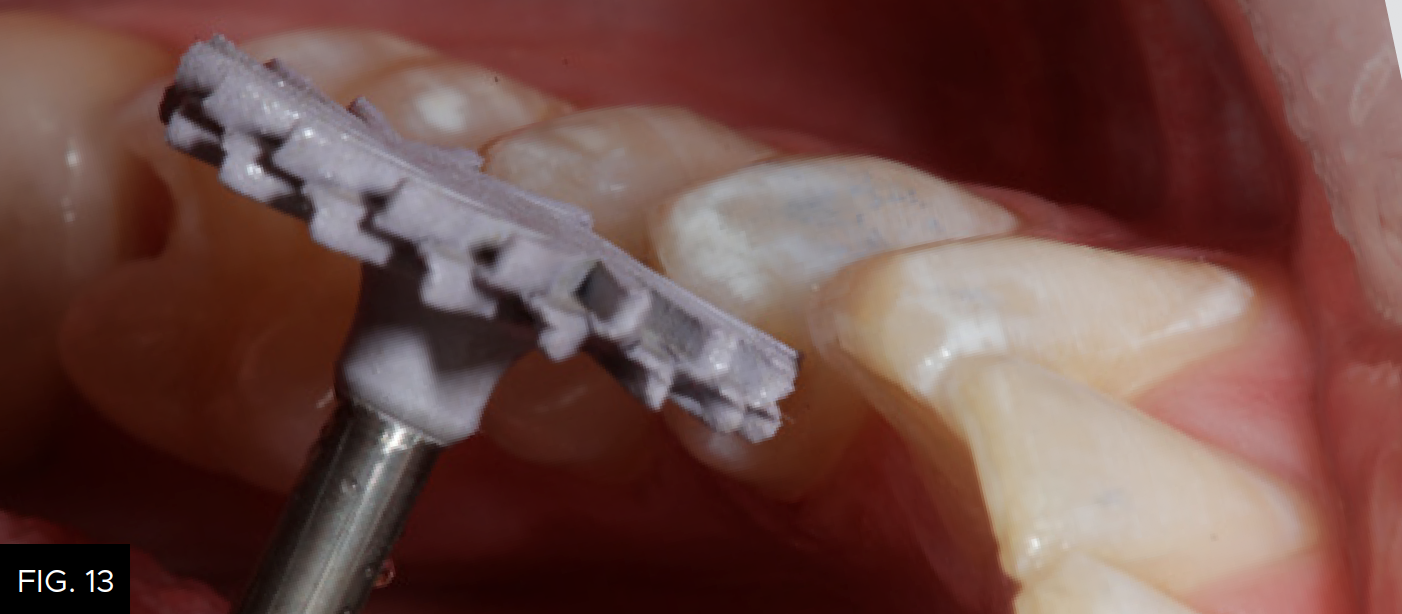

Each increment of composite material should be no more than 2 millimeters thick. The buccal increment is placed into the facial portion of the preparation, including the facial portion of the marginal ridge. The cuspal projections are sculpted and the depressions between are created using the Flexithin Mini 4. A #2 Flat Keystone brush (Patterson Dental) is lightly dipped in resin (ResinBlendLV, Clinician’s Choice), dried thoroughly with a 2X2 sponge and used to feather the material toward the margins while smoothing the surface of the composite. After fully light-curing, occlusion is checked with articulation paper and adjusted, as needed using a thin 20-fluted carbide composite finishing bur (SS White). (FIG. 12)

A 20-fluted carbide composite finishing bur (#9904, SS White) is used to adjust the occlusion prior to polishing the restoration.

When placing composite materials using the above-described technique, very little finishing should be required except at the marginal areas. Rubber polishing abrasives (A.S.A.P. Polishers, Clinician’s Choice) are used to further polish the adjusted areas. (FIG. 13)

An A.S.A.P. Pre-polisher (A.S.A.P. All Surface Access Polishers, Clinician’s Choice) is used followed by an A.S.A.P. Final High Shine Polisher to impart a high luster surface to the composite material.